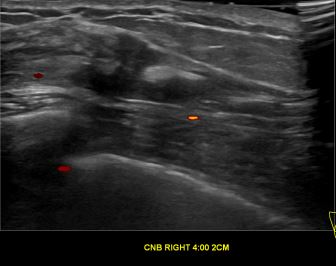

상기환자는 우측 유방 만져지는 멍우리로 내원하신 40대중반 여성분으로 의심스러운 우측혹 조직검사 시행해 유방암으로 진단되었습니다